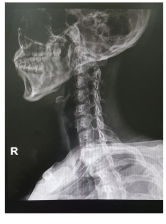

목디스크 증상 원인 치료방법 등 목 디스크 관련 정보에 대해 알아보도록 하겠습니다. 목디스크는 인간의 척추 중 경추부나 흉추부에 위치한 디스크(틀니)가 변형되어 생긴 질환으로, 경추부의 경우 목의 통증, 저림 혹은 근육 경련, 어깨와 팔의 통증, 감각상실 등이 나타나며, 흉추부의 경우 흉부의 통증, 등의 통증 등이 나타납니다. 보통은 원인불명성으로 인한 자연적인 회복을 기다리는 것이 가장 좋으며, 통증이 심한 경우 보조적으로 항통제나 근육 이완제 등을 사용합니다. 만약 압력이 심한 경우 수술이 필요할 수 있습니다.예방법으로는 바른 자세 유지와 체중 조절, 충분한 운동, 목과 등의 근육 강화 등이 있습니다.

목 디스크의 증상은 다음과 같습니다.

1. 목 통증: 목 디스크의 가장 흔한 증상으로, 목이 뻐근하고 아프며 움직일 때 통증이 심해집니다. 통증은 어깨나 팔, 손가락까지 전도될 수 있습니다.

2. 근육 경직: 목 디스크로 인해 목 주변의 근육이 긴장되고 경직되어, 목을 돌리거나 숙이기 어렵습니다. 근육 경직은 통증을 더욱 악화시킬 수 있습니다.

3. 감각 장애: 목 디스크로 인해 신경이 압박되면, 팔이나 손가락에 저림감이나 마비감이 생길 수 있습니다. 감각 장애는 일시적일 수도 있고, 지속적일 수도 있습니다.

4. 두통: 목 디스크로 인해 목과 머리 사이의 혈류가 방해되면, 두통이 발생할 수 있습니다. 두통은 보통 뒤통수나 이마에 나타나며, 움직임에 따라 심해지거나 가라앉을 수 있습니다.

5. 현기증: 목 디스크로 인해 척추동맥이 압박되면, 현기증이 발생할 수 있습니다. 현기증은 일어서거나 누워있을 때 갑자기 나타날 수 있으며, 균형감을 잃거나 구역질을 유발할 수 있습니다.